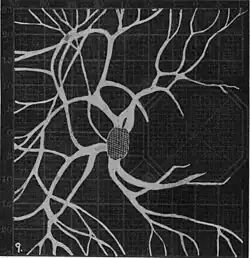

Using eccentric fixation, the more nasal parts of the angioscotoma can be plotted. -

20. Venous engorgement. 21. After pressure over internal 22. Same case, normal. 23. Scotoma after ligation of common carotid. 24. Edematous swelling of nerve and retina. 25, Normal blind spot of other eye. -

Widening of angioscotoma under various conditions (holding head lower than trunk; holding the breath; making digital pressure on the same eye; (a vein) on opposite eye; (an artery) on opposite eye).